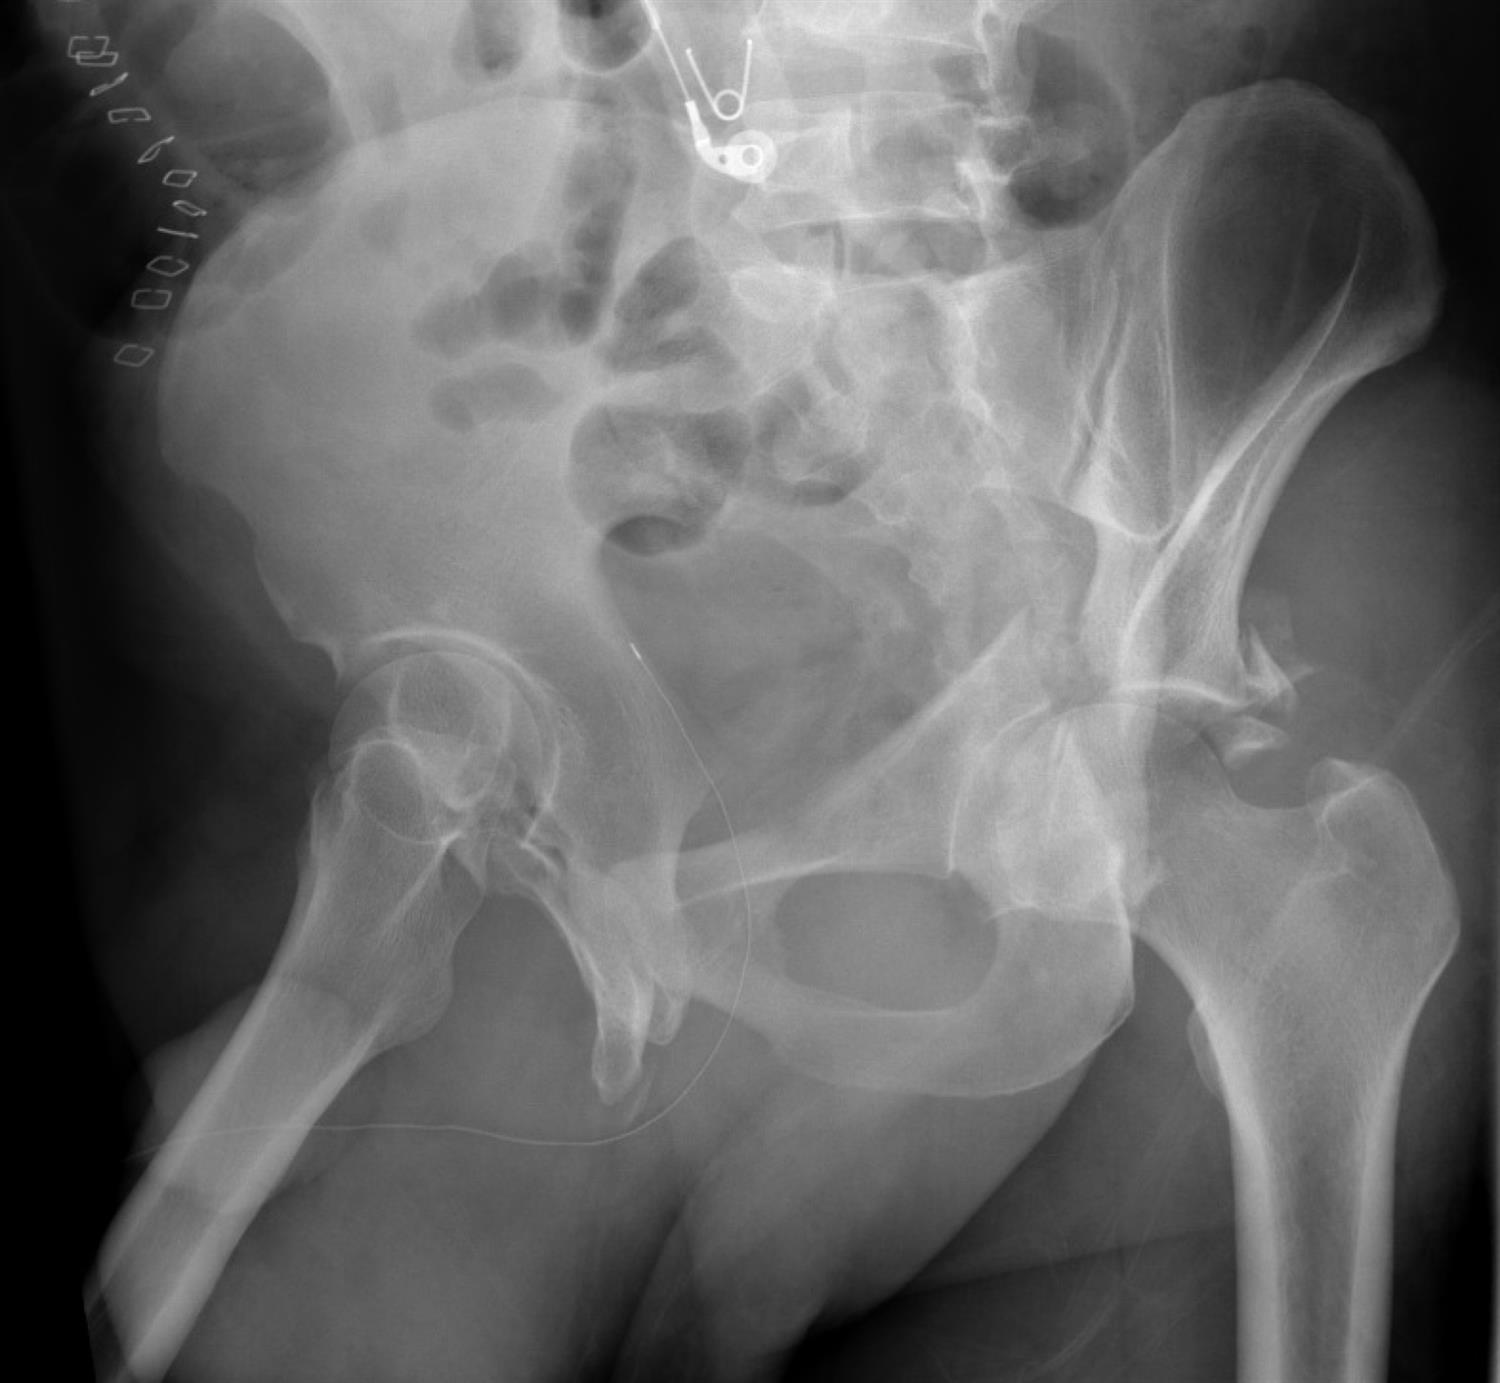

The patient has sustained a left anterior column posterior hemi-transverse acetabulum fracture. In order to properly visualize the LEFT posterior column, the most optimal radiographic Judet views would be a left iliac oblique or a right obturator oblique (these are the same image).

Acetabulum fractures are classified into 5 elementary (posterior wall, posterior column, anterior wall, anterior column, and transverse) and 5 associated fractures (associated both columns, anterior column posterior hemi-transverse, posterior wall posterior column, T-type, transverse posterior wall) patterns. Judet radiographs are very helpful in showing the extent of column and wall involvement in acetabulum fractures. These x-rays are 45-degree obliques of the hip in question and they show the profile of the obturator foramen (obturator oblique) and iliac wing (iliac oblique). To visualize the posterior column (and anterior wall), one would order the ipsilateral iliac oblique (which is equivalent to the contralateral side obturator oblique). On the contrary, the obturator oblique (and contralateral side iliac oblique) would be used to visualize the anterior column and posterior wall.

Figure A is an AP pelvis showing a left anterior column posterior hemi-transverse acetabulum fracture. Illustration A is an obturator oblique radiograph of the patient in Figure A showing an anterior column fracture. Illustration B and C are Iliac oblique radiographs showing the posterior column of the same patient.

Answer 1 and 3: A left obturator oblique radiograph would be helpful in visualizing the left anterior column and left posterior wall. Inlet and outlet views in the same obliquity would still allow visualization of those areas.

Answer 2 and 5: A right iliac oblique radiograph would be helpful in visualizing the left anterior column and left posterior wall. Inlet and outlet views in the same obliquity would still allow visualization of those areas.